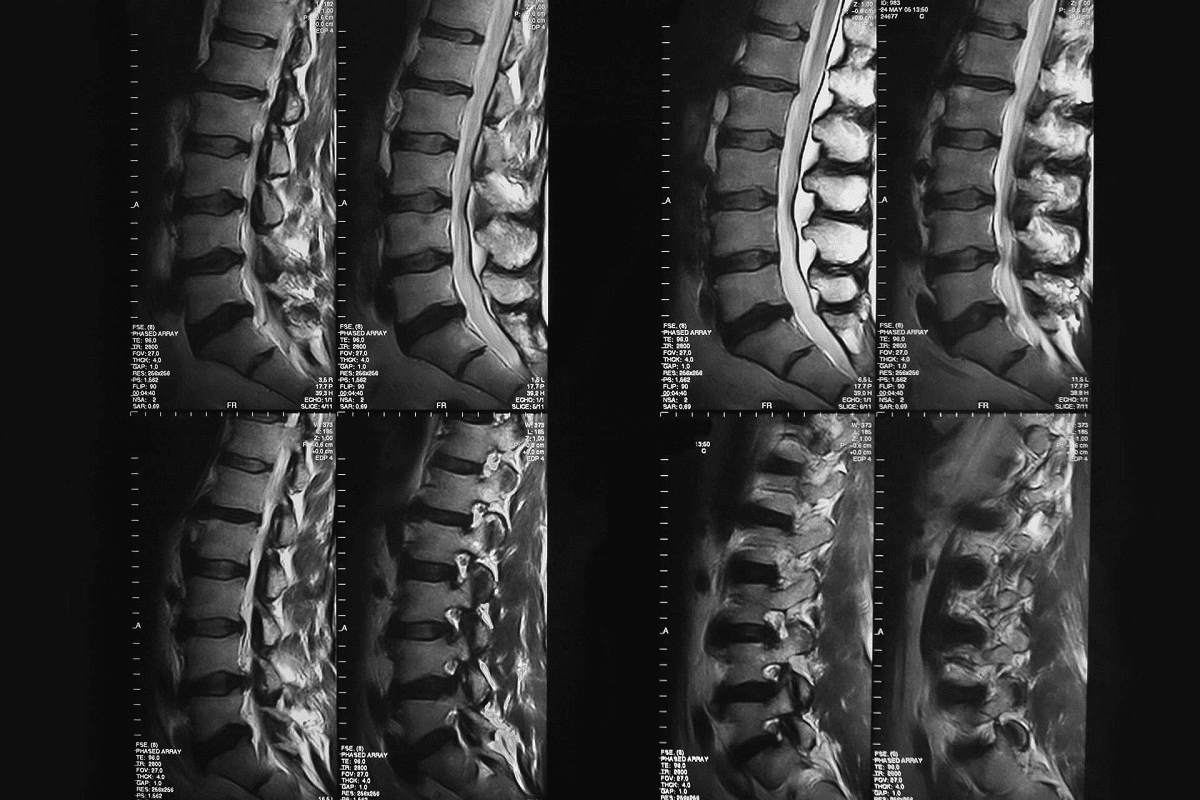

Neurosurgical Marathons: Brain and Spine Operations

Neurosurgical marathons show the progress in medical tech and surgical skills. At Liv Hospital, we focus on complex brain and spine surgeries. These need precision, patience, and a deep knowledge of the brain’s structure.

Spinal Reconstructions and Fusions

Spinal reconstructions and fusions are precise and skillful surgeries. They fix spinal deformities, stabilize the spine after injuries, or relieve spinal cord pressure. Our neurosurgical team is skilled in these operations, using the latest methods and technology for the best results and patient quality of life.

Neurological Monitoring During Long Procedures

Monitoring the nervous system during long surgeries is vital to avoid damage and ensure good outcomes. We use advanced monitoring like EEG and SSEP to check the nervous system’s function during surgery. This lets our surgeons make quick decisions and adjust their technique to reduce risks.